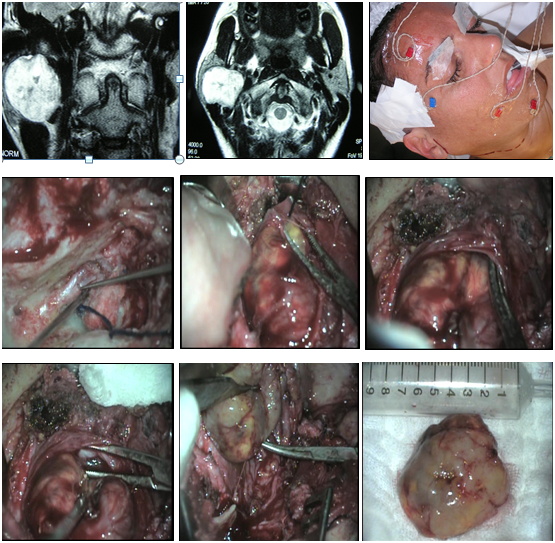

Six patients had neurilemomas located at the neck. The symptom was cervical tumor in all cases, and also disphagia in two of them. In three cases, the tumor was located at the retro-styloid carotid space. They were evaluated with tomography and magnetic resonance with contrast, and in two of them a fine needle aspiration was done with ultrasound guidance; the result was non-specific. There were not alterations in mobility of vocal cords.

In two bulky neoplasms, a displacement of the amygdala and soft palate towards the midline was observed. A transcervical approach was performed in all patients, and in two of them the exposure was extended by dissecting the posterior sector of the submaxillary gland, which was preserved.

Two tumors were originated from the cervical sympathetic chain and in another case the nerve of origin could not be specified. The resections were total and two patients had a postoperative Claude-Bernard-Horner syndrome, and one also had a “first bite” syndrome (pain in the parotid gland or in the temporomandibular joint when chewing the first time in each ingestion that decreases in successive bites) (Figure 4–6).

Figure 4 Neurilemoma originated at the cervical sympathetic chain, in the retro-styloid carotid space. Transcervical approach: complete resection.

Figure 5 Schwannoma originated at the cervical sympathetic chain in the retro-styloid carotid space. Transcervical approach: complete resection.

Figure 6 Neurilemoma originated at the carotid space.